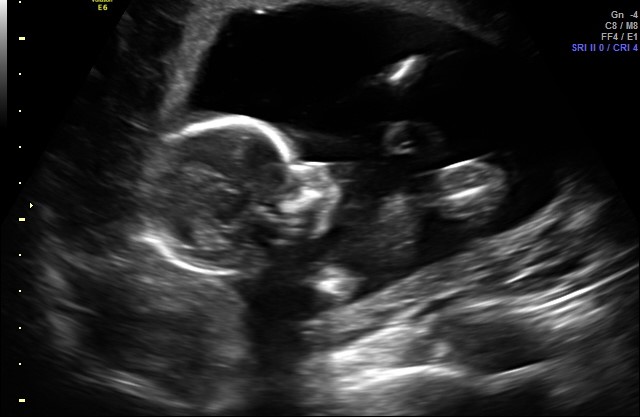

I was told a boy by this ultrasound photo, but i am having a hard time understanding the picture. Can someone help? I was sure I was having a girl, too, and this isn’t helping my confusion! https://uploads.tapatalk-cdn.com/201...d73731cca5.jpg